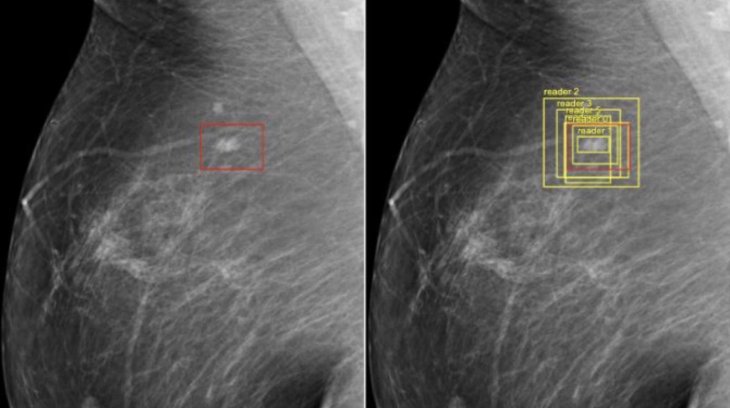

Google has just reported success in training AI to detect breast cancer more accurately than doctors do. In particular, a Google-funded study gathered independent researchers from different universities and hospitals, Google Health researchers and DeepMind engineers to compare analyses of almost 29,000 mammograms from datasets collected in the US and the UK.

The team found that the US had a 9.7% reduction in false negatives, 5.7% in false positives while the UK had a 2.7% decline in false negatives as opposed to 1.2% in false positives. AI achieved these results although it was given less information. In its control study, the company randomly selected 500 mammograms and gave them to six radiologists, along with the patients’ previous mammograms, breast cancer history, and their age.